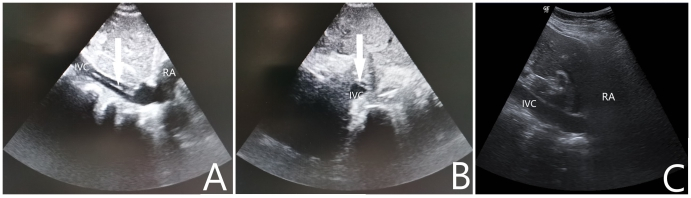

病例2:女性,69岁,农民,既往有“高血压病”“脑梗塞”“痛风”史,长期服用氨氯地平片及氯吡格雷片。主诉“胸闷胸痛2 h”于2021-10-27入院。入急诊查心电图提示存在“高侧壁、前臂、前侧壁ST段弓背向上抬高”,在送往介入室的途中出现意识不清,大动脉搏动消失,予以胸外按压、气管插管等高级生命支持。复苏期间心电监护提示室速、室颤,予以多次电除颤无法维持ROSC,征得家属同意后行ECMO支持,ECMO参数设定:转速3 400 r/min,流速3.5 L/min,吸入氧浓度100%,气流量4 L/min,成功转机后停止胸外按压,患者出现ROSC,复查床旁心电图提示“高侧壁、前臂、前侧壁ST段较前抬高”。患者出现ROSC后转运至介入室行经皮冠脉造影提示左前降支近中段次全闭,予行冠状动脉造影术+ 冠状动脉成形术+ 药物洗脱冠状动脉支架植入术+ 主动脉球囊反博泵置入,术前ECMO上机后使用肝素4 500 U,入导管室测ACT 185 s,术中追加肝素1 000 U。返回急诊ICU后给予全身肝素化抗凝,每2 h监测一次APTT,目标APTT维持在60~80 s。入院当天查心脏彩超提示LVEF:20%,左室壁运动明显减弱;入院后第1天患者口鼻腔、穿刺处大量渗血及皮下血肿,血红蛋白进行性下降,给予输红细胞悬液6 U、新鲜冰冻血浆1 000 mL并调整肝素抗凝强度使得APTT维持在50~60 s。入院后第4天复查心脏彩超提示LVEF:55%,心肌活动较前好转,并已脱离血管活性药物,遂撤除ECMO,撤机前ECMO参数设定:转速2 300 r/min,流速2.0 L/min,吸入氧浓度50%,气流量3 L/min。在拔除ECMO导管后即刻行超声筛查发现下腔静脉至右心房入口有血栓形成,长约7.2 cm,宽0.4 cm,随血流飘动(如图 2A、2B所示),筛查下肢其他部位未见明显血栓形成,遂给予依诺肝素钠100 IU/kg皮下注射每12 h一次治疗。入院后第5天行超声检查下腔静脉未见明显异常回声(如图 2C所示)。住院期间患者未出现过下腔静脉综合征或肺栓塞的症状或体征。入院后第8天患者转心内科病房,康复后出院随访1个月未遗留任何中枢神经系统并发症。

| A:下腔静脉纵向超声扫描显示下腔静脉至右心房入口有血栓形成;B:下腔静脉水平超声扫描显示下腔静脉内漂浮的血栓影;C:经治疗后超声在下腔静脉未见明显异常回声;RA:右心房,IVC:下腔静脉 图 2 撤离ECMO后即刻行下腔静脉超声检查 |